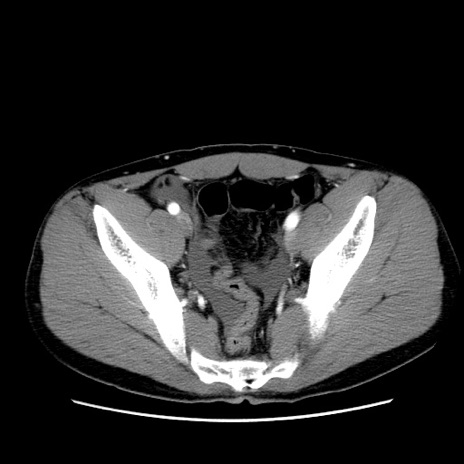

症例36(横断像)

【症例】20歳代 男性

【主訴】心窩部痛

【現病歴】今朝より上腹部痛あり。一旦軽快していたが再度出現したため救急要請。昨日夕に白身の魚を含む刺身を食べた。

【身体所見】BP 136/89mmHg、HR 74/min、BT 37.0℃、腹部:膨満、軟、心窩部に圧痛あり。反跳痛なし、筋性防御なし、腸雑音やや亢進あり。

【データ】WBC 17700、CRP 0.48